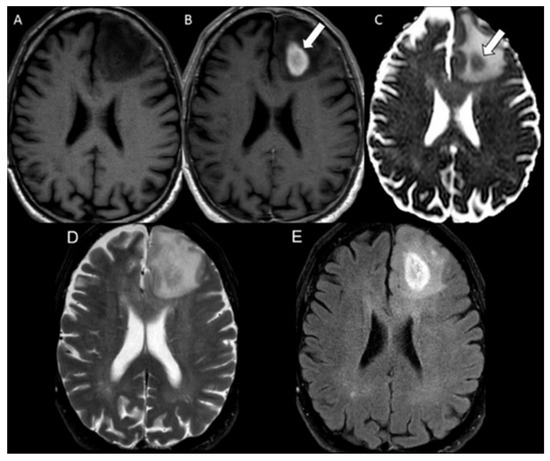

| Bevacizumab | 1.00 | N/A |

| Progressive glioblastoma | 0.59 | 0.41–0.70 |

| Radiation necrosis | 0.98 | 0.95–1.00 |

| Bevacizumab | 21 | 0.39 ± 0.10 |

| Progressive glioblastoma | 49 | 1.07 ± 0.22 |

| Radiation necrosis | 58 | 0.66 ± 0.14 |